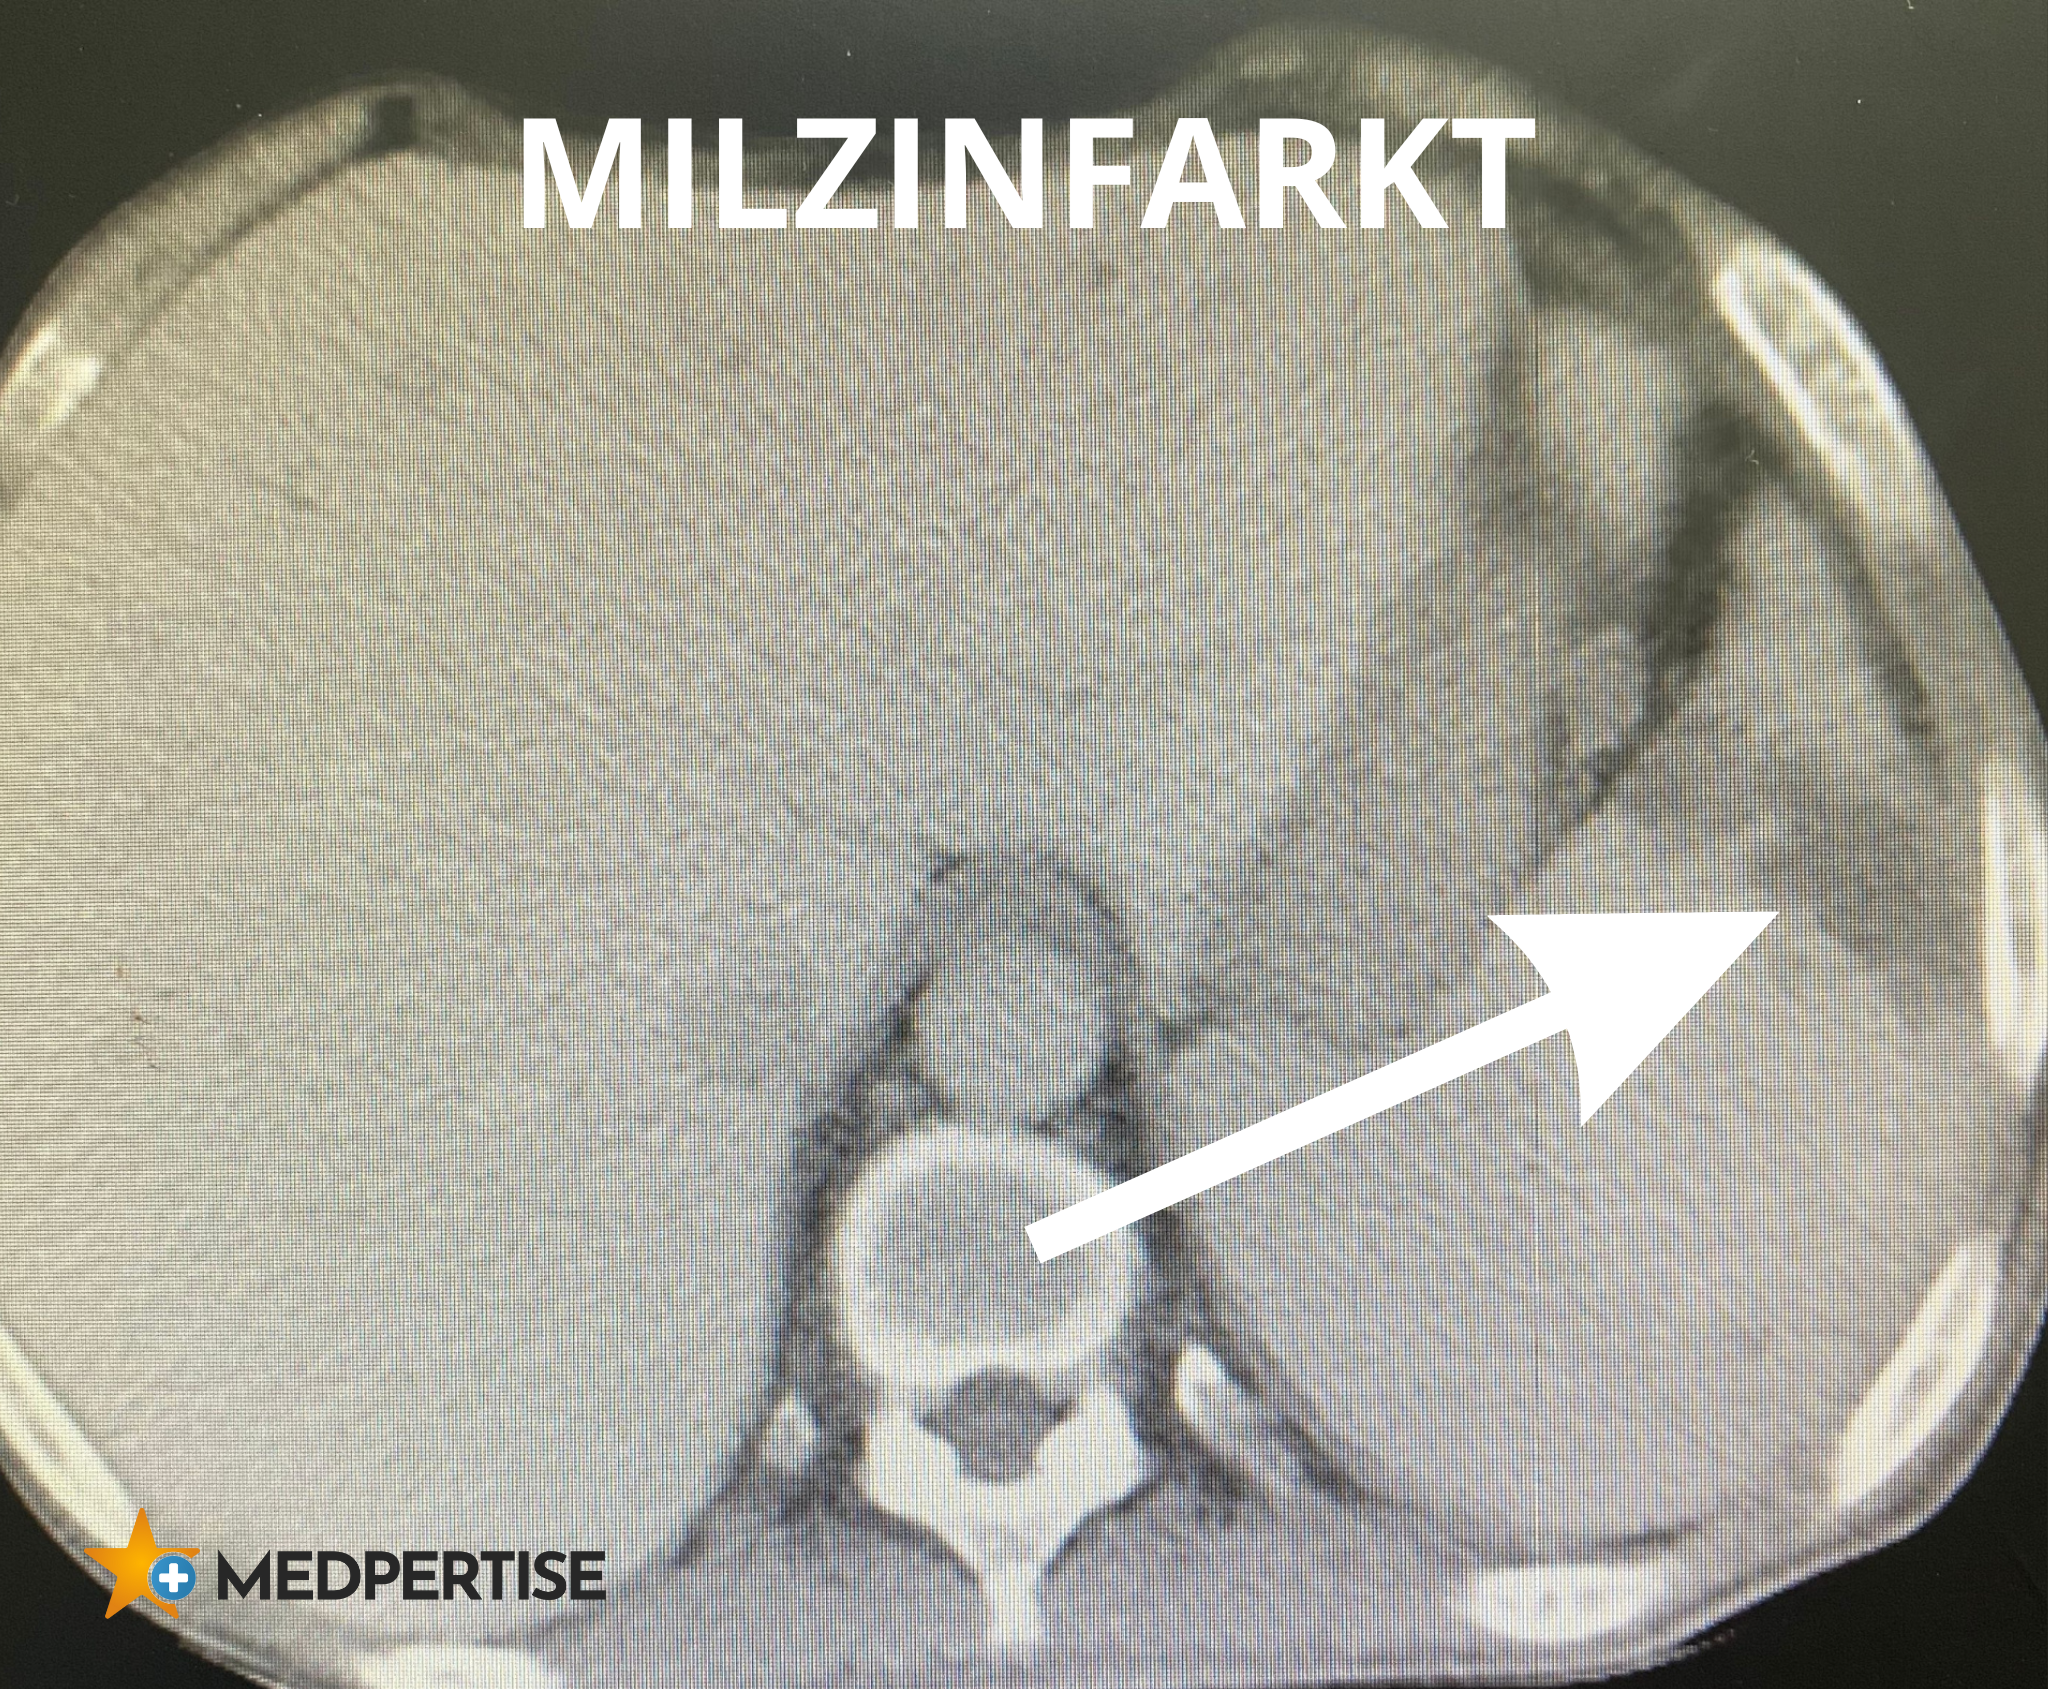

Bestätigt wird die Verdachtsdiagnose Milzinfarkt mit Hilfe einer sogenannten Doppler-Ultraschalluntersuchung (Doppler-Sonografie). Dabei können die Gefäße der Milz sichtbar gemacht und die Durchblutung des Organs beurteilt werden. In der Regel reicht diese Ultraschalluntersuchung aus. Bei Unklarheiten bezüglich der Diagnose kann zusätzlich eine Computertomografie (CT) erfolgen.